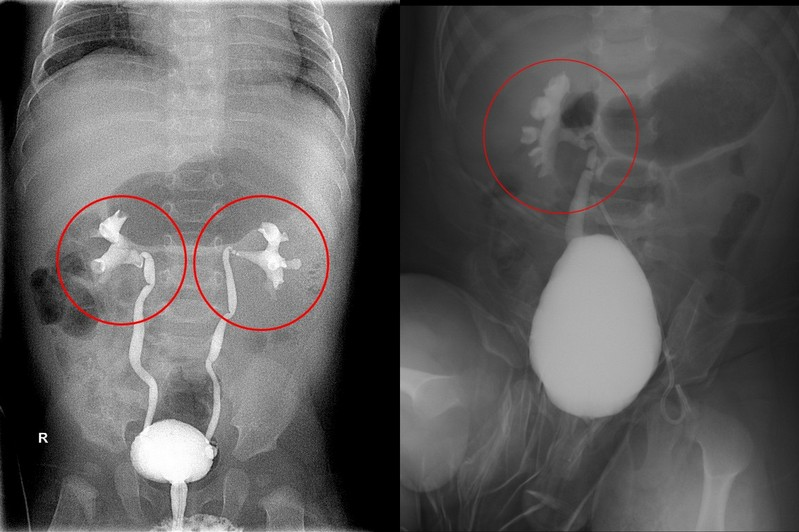

VCUG(排尿膀胱尿道攝影檢查)是放置導尿管後,打顯影劑看尿流情況,可以依輸尿管的模樣診斷出疾病程度,劃分為一到五級,四級和五級屬於較嚴重的類型。不滿一歲的胡小弟和陳小弟,先後在花蓮慈院檢查出患有膀胱輸尿管逆流,其中胡小弟的兩側輸尿管為三級,陳小弟則是右邊單側四級、左邊正常。楊筱惠醫師指出,小兒的膀胱輸尿管逆流情形其實可能隨著孩子長大而好轉,不一定要在剛發現時直接手術,若是曾經有泌尿道感染的個案,可以先口服抗生素治療,等待和觀察抗逆流功能是否進步;但二位小朋友在持續吃了幾個月的抗生素後,依然反覆感染發燒,所以都接受了膀胱輸尿管逆流的治療手術。

圖說:經VCUG(排尿膀胱尿道攝影檢查)診斷疾病程度,胡小弟兩側輸尿管為三級,陳小弟則是右邊單側四級、左邊正常。